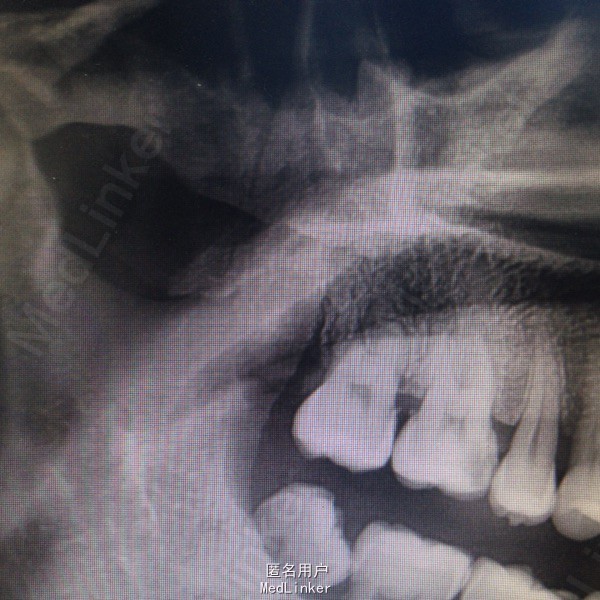

18拔牙创愈合良好,牙龈无红肿,无压痛。17牙体完整,颌面见可疑隐裂纹,扣痛(-),无松动。16近中颌面龋,探近髓顶,扣痛(+)。行局部牙片检查,拔牙创,无残根,16近中根尖暗影。远中颌骨骨折征象。复查全景片提示牙槽突骨折,远总向移位,局部骨不愈合。

1.右上颌牙槽突骨折伴慢性炎症 2.16慢性根尖周炎 3.17隐裂慢性牙髓炎? 处理:局麻拔除右上颌牙槽突骨折片,17调磨观察,16根管治疗。